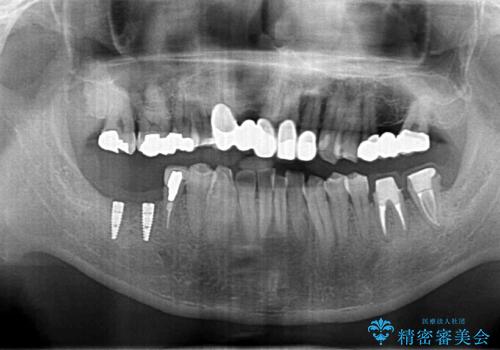

- 短期間で歯並びを治したいとのこと。期間が短ければセラミックでかぶせる治療できれいにするのでも構わない。虫歯の治療もすべてお願いしたいとのことでした。

右下の奥歯は残せない可能性を説明しました。

また、歯並びの矯正をするのではなければ、右上の八重歯は、犬歯を抜くか、奥に入っている歯を抜くかになるとお伝えしました。結果、根の長い犬歯を残して右上の前歯を抜歯しブリッジにしました。また、前歯の神経は極力取らないで治療を行いました。(結果神経を取る治療は前歯には行っておりません)

右下奥歯二本はインプラントにしました。(横浜桜木町歯科院長 大元先生による)

また、銀歯はすべてやり直しを行い、セラミックでやり替えを行いました。

前歯の治療を先に行い、見た目を改善した後、奥歯の治療を行いました。